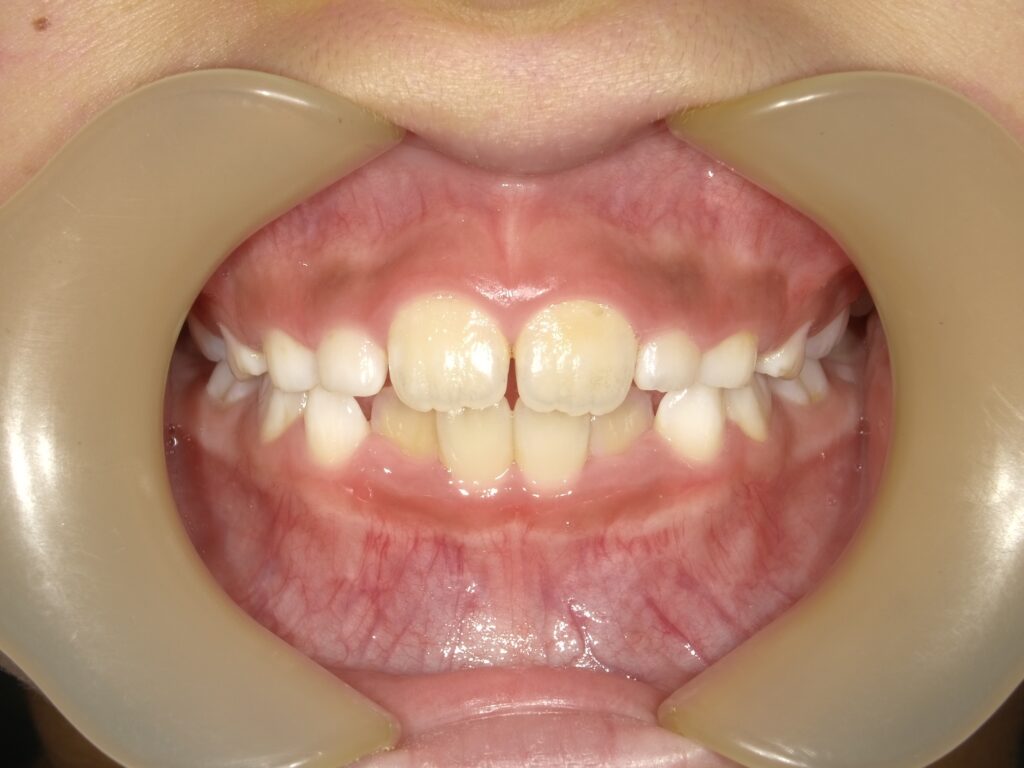

ご兄弟で同じ歳の時期に撮影したものです。歯の形やある程度のアーチはやはり似ていますが、下顎前歯の傾斜や生え変わりなどの違いがあります。

兄弟姉妹でも、歯の大きさや生える角度、あごの骨格には違いがあります。

たとえば、一方が「出っ歯」で、もう一方が「受け口」という場合もあり、治療法や始める時期が異なるのは当然です。